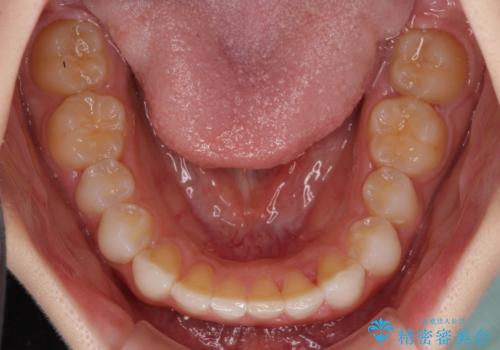

デコボコと深い咬み合わせの改善 インビザラインによる矯正治療

- 口元のデコボコと深い咬み合わせ(ディープバイト)を気にして来院された患者様です。

インビザラインによる上下歯列の拡大と、IPR(歯と歯の間を削る)にるスペースの獲得により、口元のデコボコとディープバイトを改善することとしました。

インビザラインは、装着していない時間がどれだけ短いかが、治療期間を大きく左右します。こちらの患者様は1日22時間以上、毎日欠かさず装着してくださったため、1年強という短期間で満足のいく歯列に整えることができました。